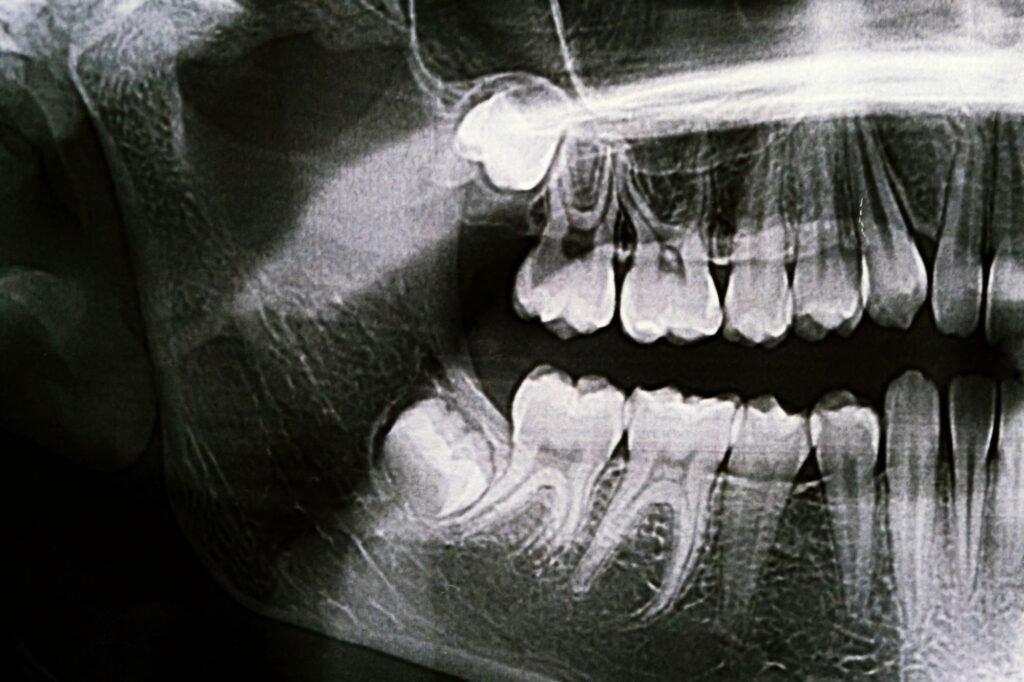

Muelas del juicio: cuándo vigilar y cuándo operar

Muelas del juicio: qué son y por qué a veces dan problemas Las muelas del juicio son los últimos dientes en aparecer y, por eso mismo, muchas veces salen cuando ya queda poco espacio en la boca. Lo más habitual es que erupcionen entre el final de la adolescencia y el comienzo de la vida […]